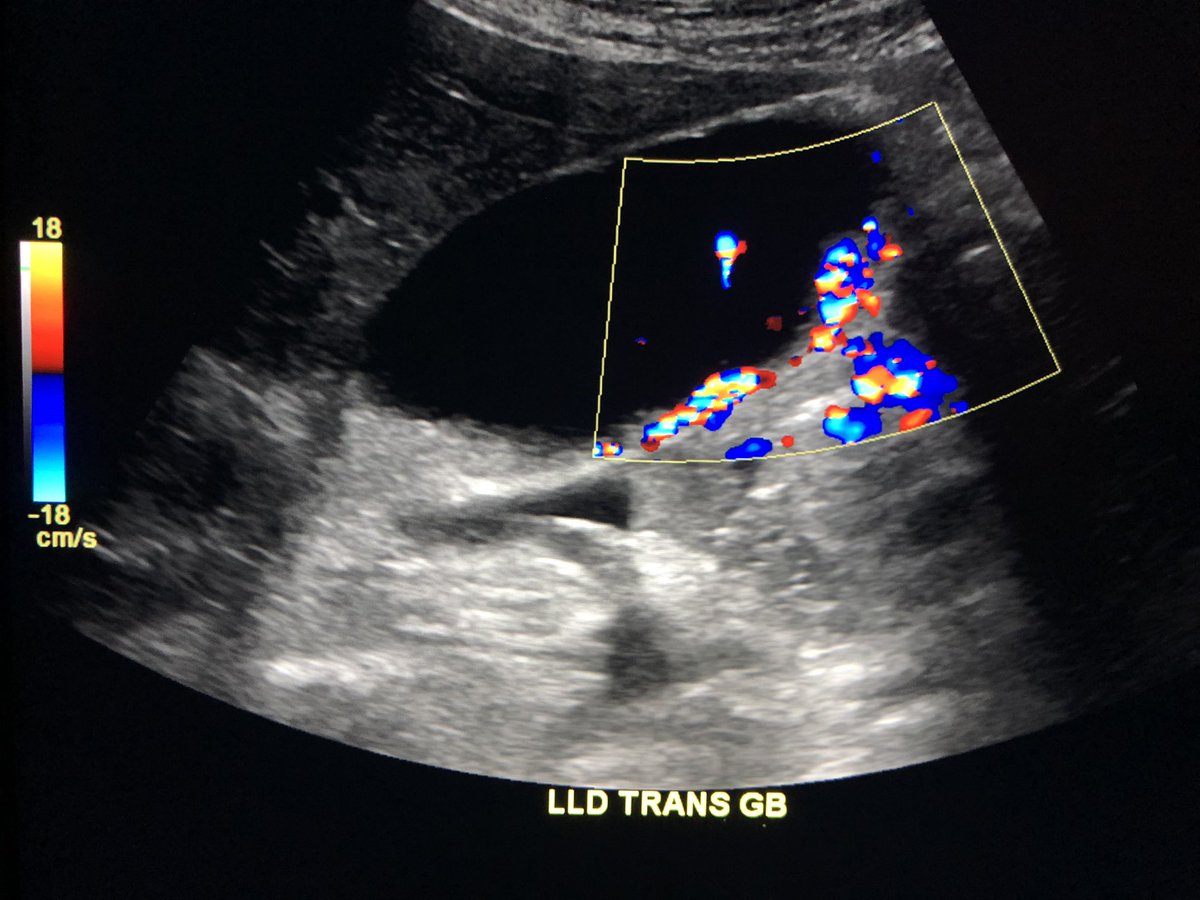

The technologist was concerned that these vascular masses were adenomatous polyps. Question 1. Is this vascular? Question 2. What would you do next?pic.twitter.com/9faka4mEwD

Prikaži ovu nitHvala. Twitter će to iskoristiti za poboljšanje vaše vremenske crte. PoništiPoništi